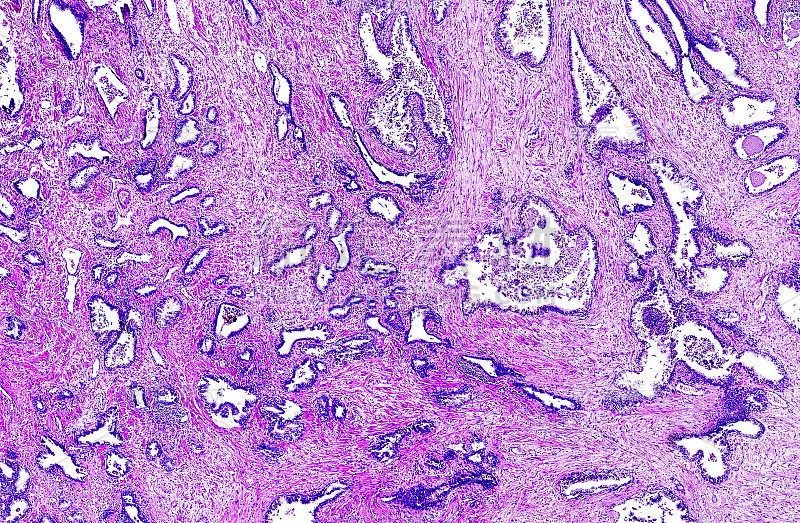

人类前列腺肥大详情